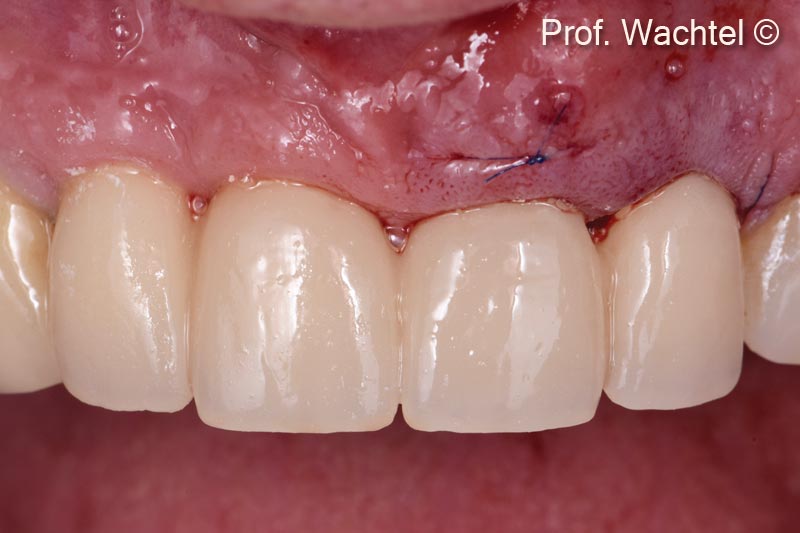

6. The clinical view shows the final treatment result after extraction of tooth #21. Implantation, immediate restoration and site development are performed according to the Multi-Layer Technique (MLT), and new full ceramic crowns are placed in #12 - #22